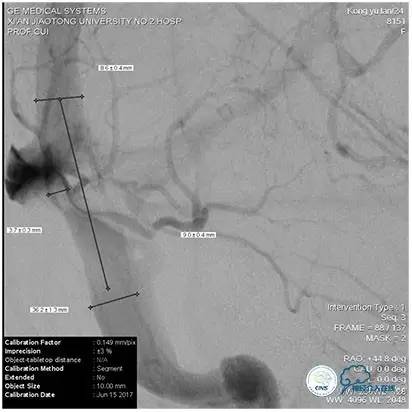

2、术中再次测量血管直径,选择恰当球囊缓慢扩张,避免过度扩张,造成静脉窦与颅骨剥离形成硬膜外血肿;

3、球囊扩张态势下行同侧颈内动脉或椎动脉造影,了解穿支静脉回流状况,如穿支回流缓慢,则选择比静脉窦测量直径小1~2mm的支架;术后发生皮层静脉回流受阻所导致的的梗死、出血风险要小。